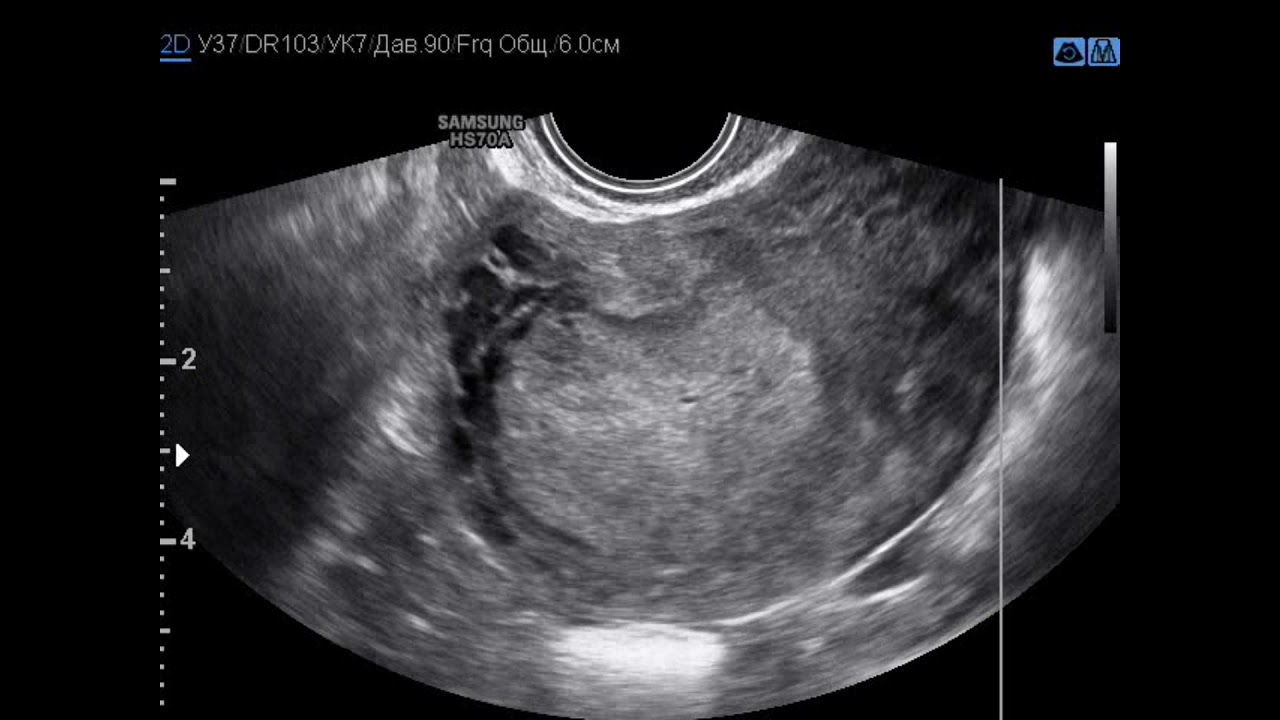

WebПлацентарный полип после родов: симптомы и лечение, в матке, удаление, выскабливание, выделения, эндометрия, признаки, на УЗИ, вышел, как лечить. WebПлацентит. Симптомы. Диагностика. Что делать при диагнозе Плацентит. Консервативное лечение и операции. Платные и бесплатные клиники, в. WebПреждевременная отслойка плаценты может развиться, как в течение беременности, так и в процессе родов. Частота данной патологии встречается в.